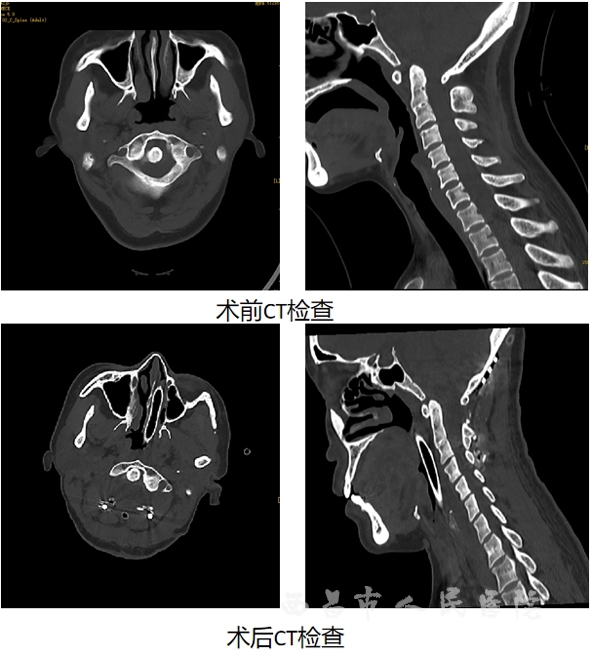

近日,西昌市人民医院神经外科在电生理监测技术下,为一患者成功实施高难度寰枢椎脱位复位术。目前,患者状态良好,能自行下地行走,肢体肌力正常,现已康复出院。这是我院神经外科团队在神经脊椎脊髓疾病诊疗上的又一次成功案例。

据悉,该患者42岁,近来被颈部疼痛伴四肢麻木、无力等不适所困扰,曾到多家医院就诊给予康复理疗后效果不佳,症状逐渐加重,严重影响了日常生活和工作。经过四处辗转、多方咨询后来到我院就诊,在完善相关检查后发现患者寰枢关节椎脱位,C0/1融合,脊髓受压。颈椎的问题出在颈椎第一、二节,脊髓压迫位置非常高,一旦颈椎脊髓压迫部位进一步加重可导致全身瘫痪甚至呼吸心跳停止等严重后果,手术风险极高。

考虑到该患者手术风险和麻醉风险较大,神经外科脊柱组团队、麻醉科团队以及手术室团队对患者病情进行多次术前讨论,积极与患者及家属沟通,精心制定详细的手术和治疗方案。经周密的术前准备,神经外科团队在电生理全程监测下,为患者实施“后正中入路C1/2脱位复位+植骨融合枕颈钉棒内固定术”,术中出血约50ml。手术通过团队的共同努力和密切配合,在相关科室强有力的技术支持和保障下,安全顺利完成。经后续精心治疗和细心护理,患者恢复良好。